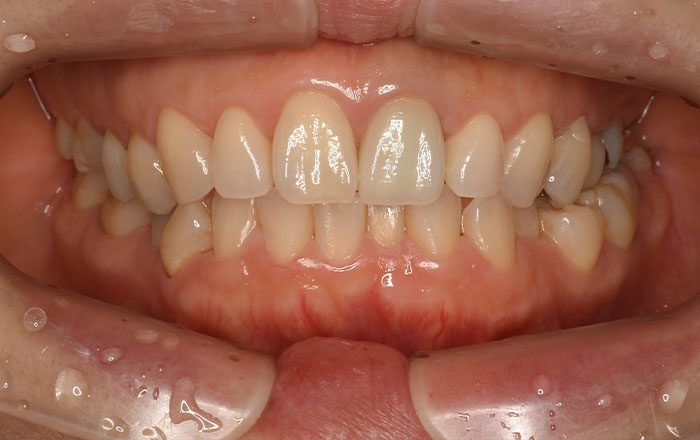

スケーリング(保険適用)

スイス・EMS社製の超音波スケーラーで、歯の表面や歯と歯茎の間にある歯垢や歯石を痛みなく取り除きます。